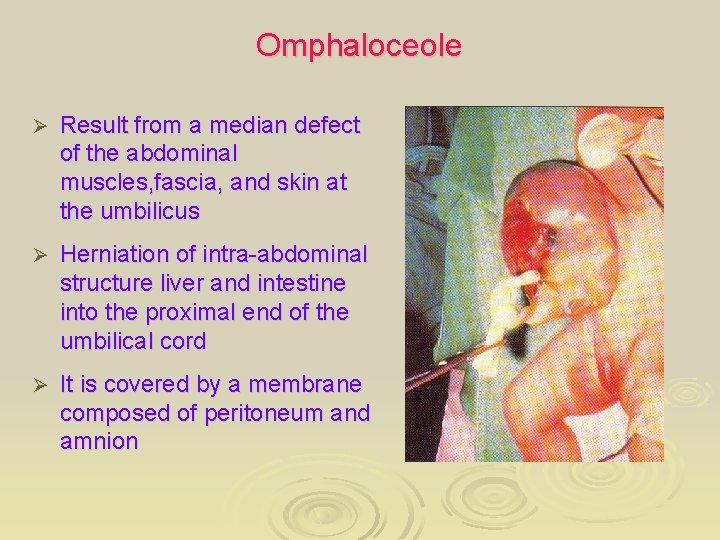

Omphaloceole Ø Result from a median defect of the abdominal muscles, fascia, and skin at the umbilicus Ø Herniation of intra-abdominal structure liver and intestine into the proximal end of the umbilical cord Ø It is covered by a membrane composed of peritoneum and amnion

Omphalocele Ø Ø Ø Type: External Region/Structure: Trunk Definition: Protrusion of intra -abdominal viscera into the umbilical cord with viscera contained in a thin translucent sac of peritoneum and amnion Notes: The condition may present with ruptured sac Related Term : Exomphalos Arrow: Attached Placenta